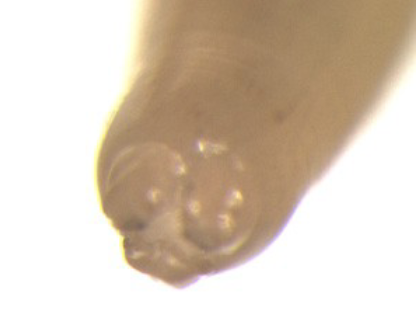

what is shown here?

Ascaris lumbricoides has three lips with teeth to help attach to intestinal wall